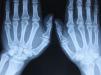

Radiología simpleHasta el momento es la única prueba de imagen validada para valorar el grado de afectación articular en la APso, la progresión y la respuesta terapéutica, pero no es útil para valorar la afectación de otras estructuras musculoesqueléticas como las entesis, los tendones y ligamentos. La solicitud de radiografías a un paciente determinado para valorar el nivel de afectación articular se realizará según la clínica y la exploración física del paciente, de forma dirigida (fig. 1).